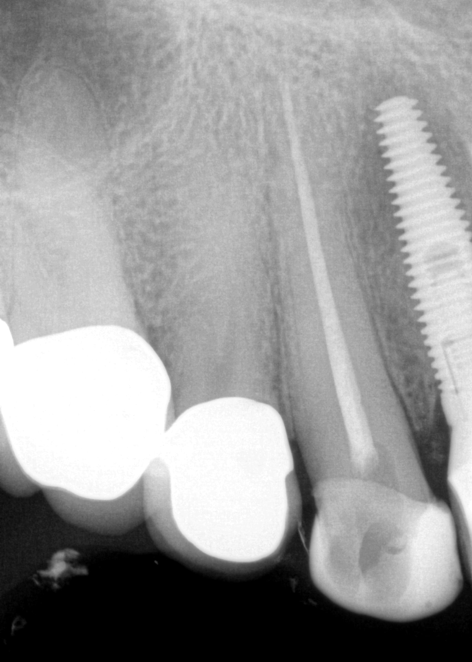

Fig 1. A preoperative radiograph was taken, the patient was administered local anesthetic, and a digital estimated measurement was recorded for initial working length.

Figure 1

A patient presented with acute pain and facial swelling. Tooth No. 6 was positive to percussion, without sensitivity to air, sweets, or temperature stimulus. Treatment options were discussed with the patient. The decision was to complete endodontic therapy to eliminate the pain (Figure 1). Definitive long-term final-restoration treatment options were presented using a fiber post and core with full-coverage CAD/CAM crown.